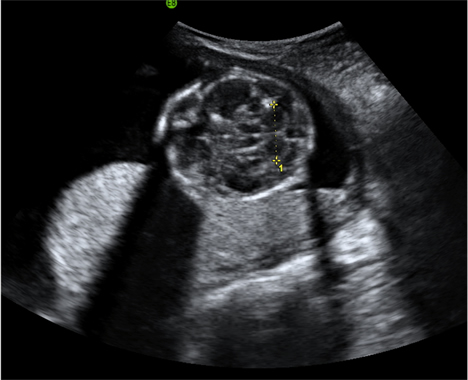

| Fig 2 Anterior placenta |

This image shows the anterior placenta, seen as the area of mid range echoes attached to the anterior wall of the uterus.